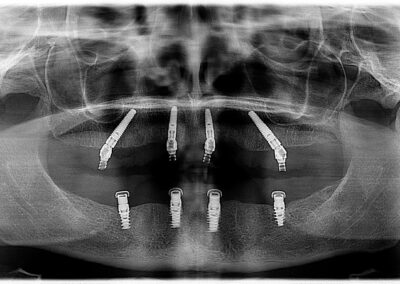

These natural teeth are non-restorable, but with the technology available we provided a very functional and esthetic result. The case was treatment planned using a fully guided implant system, Nobel Biocare. The maxilla (upper) are supported by 4 implants. This technique is referred to as the All-on-4. The maxilla is a screw retained wrap around prosthetic and removed only by a dental professional. The patient will have the teeth removed and placed back onto the implants every 12-18 months. This is an easy appointment done in less then an hour. This prosthetic is as close to having natural teeth as a patient can get. The mandibular teeth (lower) are supported by 4 implants. This lower denture is removable and the patient doesn’t sleep with this in their mouth at night. This type of denture is more of a traditional denture but because it is implant supported the patient is able to function as close to normal as possible. The outcome was very predictable because of the technology Dr. Dove has invested in. This provides our patients with a very great service.

After: